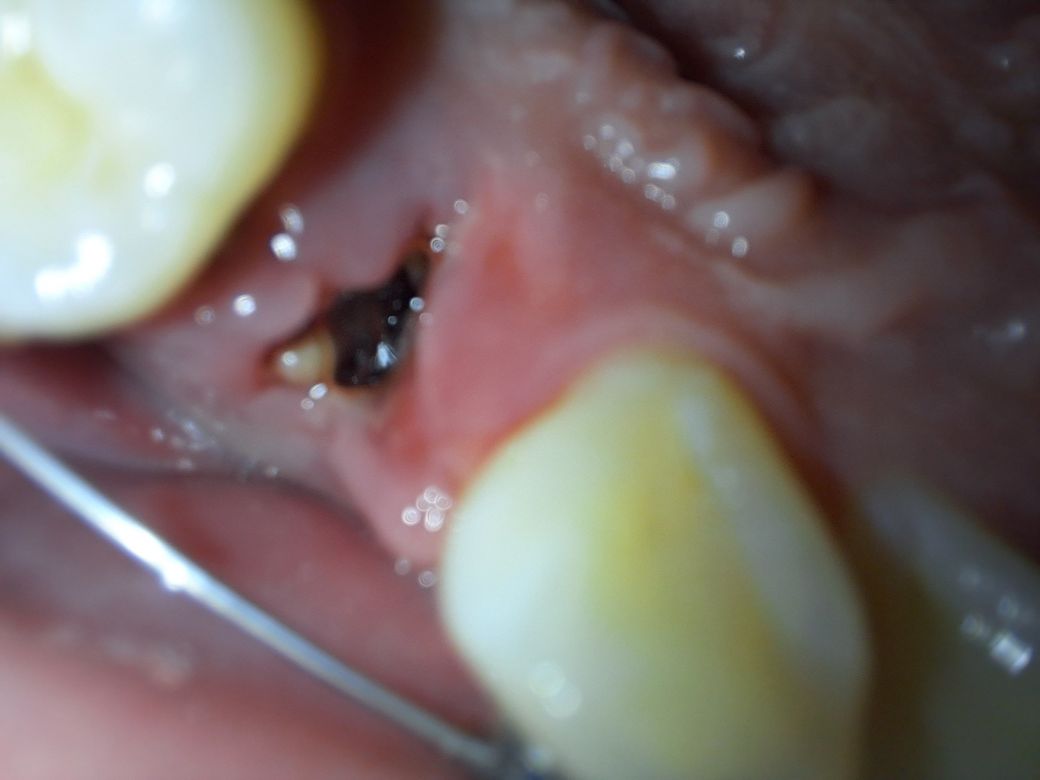

발치후 내부에 뭔가 있습니다.

치아 교정을 위해 발치를 하고 하루하고 좀 더 지났는데 약한 통증이 계속 느껴집니다..반대쪽은 아무 감각도 없고요..

어제 당장에는 안아프던게 오늘 갑자기 통증이 느껴지기 시작하내요.치과를 가는 편이 좋을까요?

발치를 하고 난 뒤에 발치와에 이물질이 들어가서 나오지 않을도 있습니다 .

또한 발치한 부위에 혈병이 떨어져 나가서 내부가 비게 되어도 사진과 같은 모습을 보일수 있습니다.

지금 사진으로 보아 정상적인 치유과정으로 보입니다. 노랗게 보이는 것은 뽑은 자리 부근 잇몸에

딱지 않은 것으로 보면 됩니다. 통증이 약간 있으면 진통제 복용하시고 심한 통증이 있으면 염증을 의심해야

하니 도로 치과 내원하는 것이 좋습니다.

사진이 흐려서 정확히 보이질 않아 판단이 어렵습니다.

노란것은 음식물일수도 있고, 잇몸의 일부일수도 있습니다. 우선 정확히 봐야 판단이 가능하기 때문에, 통증이 몇일 지속된다면 치과에 방문해보시기 바랍니다. 감사합니다.